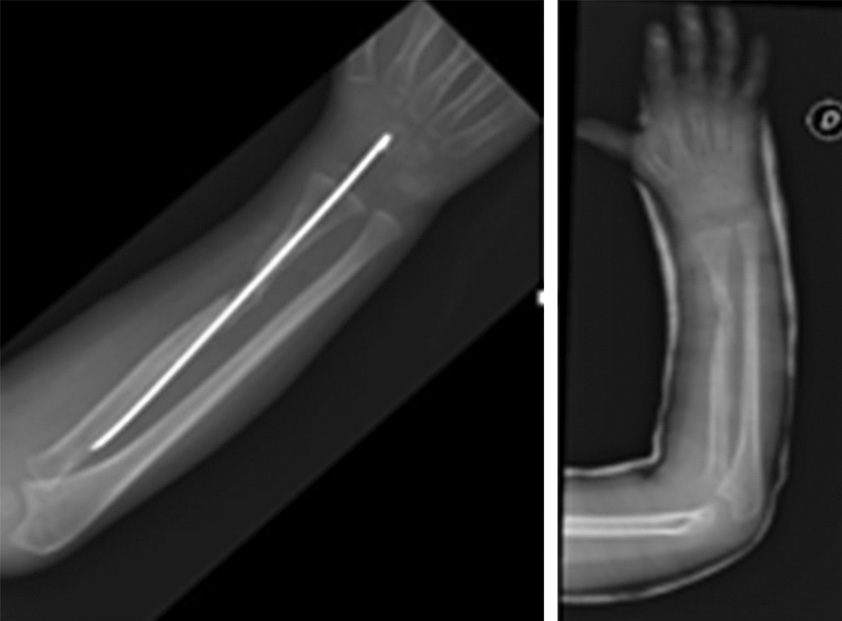

Через 10 дней после выписки из больницы пациент вновь обратился в отделение неотложной помощи с нарастающей болью в ноге, откуда была получена кость. Установлен диагноз местной гематомы, вызванной поражением межкостной артерии. В связи с этим проведена экстренная сосудистая операция для дренирования гематомы и закрытия поражения артерии. В феврале 2016 г., всего через 10 дней после последней операции, у пациента снова появилась боль в ноге. Было решено обратиться за советом в другой институт, в котором диагностировали псевдоаневризму пораженной артерии, по поводу которой проведена новая экстренная сосудистая операция. Между тем рентген не показал консолидации трансплантата в предплечье. После неудачи повторного введения факторов роста костного мозга в декабре 2016 г. выполнена новая операция с санацией очага несращения и трансплантацией трупной кости с фактором роста костного мозга, стабилизированной спицами Киршнера (рис. 5, 6).

Рис. 5. Отсутствие на рентгенограмме консолидации аутологичной малоберцовой кости

Рис. 6. Рентгенограмма после санации очага несращения и трупный костный трансплантат с костномозговым фактором роста, стабилизированный спицами Киршнера